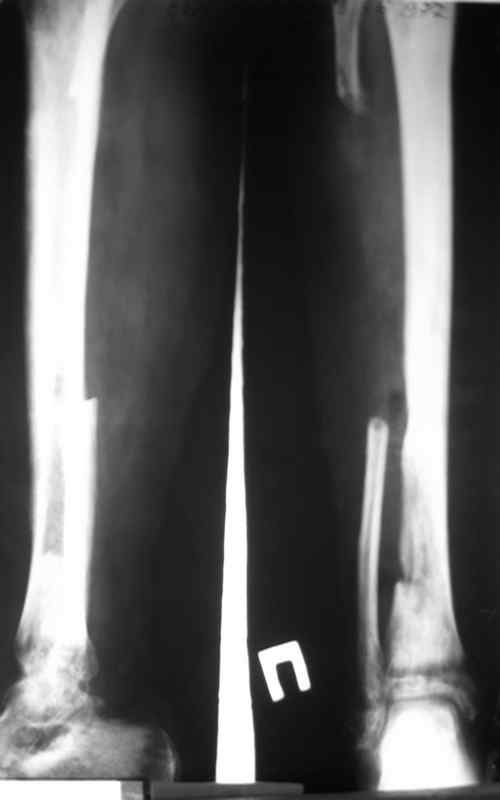

Доброго времени суток, коллеги! Сегодня поступил больной с остеомиелитом

голени, 29 лет.

Травма - январь 2007 года, <Открытый перелом малоберцевой кости,с

повреждением малоберцевого нерва>. Первичных снимков нет. лечился в

одной из районных больниц xUSSR. Обратился ко мне в сентябре 2007 года,

сжалобами на наличие свищей,неопорность конечности.Был направлен после

выполнения фистулографии (см. фото) в областной  центр по лечению

остеомиелита. Там была выполнено 2 операции:  резекция малоберцевой

кости, и повторный дебридмент. Последнее вмешательство около месяца

назад. Послеоперационные снимки на фото. В течении месяца получал